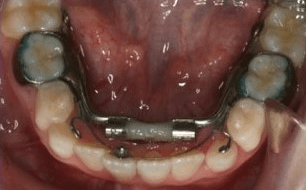

The Williams appliance is banded on the deciduous second molars in the “early” mixed dentition, and on the permanent first molars in the “late” mixed dentition. It consists of a special midline expansion screw, attachments contacting the lingual surface of all of the posterior teeth, and a nickel titanium arch wire that can be activated against the lower incisors. Separators are places on the patient while the appliance is being fabricated using the indirect banding technique.

A standard orthodontic button is bonded to the most instanding lower incisor or incisors. The lower arch is isolated for moisture control and the bands cemented using orthodontic glass ionomer band cement. If the appliance is banded on the deciduous second molars these teeth should be acid etched prior to cementation to enhance band retention. The lingual arch wire is activated by engaging it beneath the button on the incisor or incisors.

A very common modification of the Williams appliance is to use buccal tubes on the molar bands when the appliance is placed on the permanent first molars. Delta Force brackets can be placed on all of the permanent teeth that have erupted anterior to the permanent first molars. A .020 x .020 thermal activated, multi-gradient force, nickel titanium arch wire is used in conjunction with the Williams appliance to level, align, and torque the teeth as the arch is being developed.